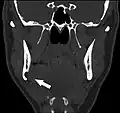

Stafne bone cavity seen on coronal CT